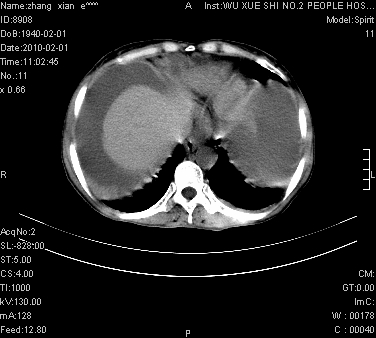

标题: CT24434:70岁 女 腹胀,腹水原因待查 [打印本页]

大量腹水,脾脏囊性占位,子宫颈占位,右侧腹股沟淋巴结肿大,建议+c,先查妇科。

大量腹水,脾囊肿可能性大,建议增强

大量腹水,右肾、脾囊肿可能性大          考虑左侧附件区占位,建议增强